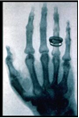

Министерство образования и науки РФ Федеральное агентство по образованию ГОУ ВПО ЮУрГУ Кафедра физической химии Реферат по курсу КСЕ: “Рентгеновское излучение” Выполнил: Наумова Дарья Геннадиевна Ком-140 Проверил: Доцент, К. Т.Н. Танклевская Н.М. Челябинск 2010 г. Содержание Введение Глава I. Открытие рентгеновского излучения Положение на шкале электромагнитных волн Получение Взаимодействие с веществом Биологическое воздействие Регистрация Применение Как делают рентгеновский снимок Естественное рентгеновское излучение Глава II. Рентгентография Применение Метод получения изображения Преимущества рентгенографии Недостатки рентгенографии Рентгеноскопия Принцип получения Преимущества рентгеноскопии Недостатки рентгеноскопии Цифровые технологии в рентгеноскопии Многострочный сканирующий метод Заключение Список использованной литературы ВведениеРентге́новское излуче́ние - электромагнитные волны, энергия фотонов которых определяется диапазоном энергией от ультрафиолетовых до гамма-излучений, что соответствует интервалу длин волн от 10−4 до 10² Å (от 10−14 до 10−8 м). Как и видимый свет, рентгеновское излучение вызывает почернение фотопленки. Это его свойство имеет важное значение для медицины, промышленности и научных исследований. Проходя сквозь исследуемый объект и падая затем на фотопленку, рентгеновское излучение изображает на ней его внутреннюю структуру. Поскольку проникающая способность рентгеновского излучения различна для разных материалов, менее прозрачные для него части объекта дают более светлые участки на фотоснимке, чем те, через которые излучение проникает хорошо. Так, костные ткани менее прозрачны для рентгеновского излучения, чем ткани, из которых состоит кожа и внутренние органы. Поэтому на рентгенограмме кости обозначатся как более светлые участки и более прозрачное для излучения место перелома может быть достаточно легко обнаружено. Рентгеновская съемка используется также в стоматологии для обнаружения кариеса и абсцессов в корнях зубов, а также в промышленности для обнаружения трещин в литье, пластмассах и резинах. Рентгеновское излучение используется в химии для анализа соединений и в физике для исследования структуры кристаллов. Пучок рентгеновского излучения, проходя через химическое соединение, вызывает характерное вторичное излучение, спектроскопический анализ которого позволяет химику установить состав соединения. При падении на кристаллическое вещество пучок рентгеновских лучей рассеивается атомами кристалла, давая четкую правильную картину пятен и полос на фотопластинке, позволяющую установить внутреннюю структуру кристалла. Применение рентгеновского излучения при лечении рака основано на том, что оно убивает раковые клетки. Однако оно может оказать нежелательное влияние и на нормальные клетки. Поэтому при таком использовании рентгеновского излучения должна соблюдаться крайняя осторожность. Глава I. Открытие рентгеновского излученияОткрытие рентгеновского излучения приписывается Вильгельму Конраду Рентгену. Он был первым, кто опубликовал статью о рентгеновских лучах, которые он назвал икс-лучами (x-ray). Статья Рентгена под названием "О новом типе лучей" была опубликована 28-го декабря 1895 года в журнале Вюрцбургского физико-медицинского общества. Считается, однако, доказанным, что рентгеновские лучи были уже получены до этого. Катодолучевая трубка, которую Рентген использовал в своих экспериментах, была разработана Й. Хитторфом и В. Круксом. При работе этой трубки возникают рентгеновские лучи. Это было показано в экспериментах Крукса и с 1892 года в экспериментах Генриха Герца и его ученика Филиппа Ленарда через почернение фотопластинок. Однако никто из них не осознал значения сделанного ими открытия и не опубликовал своих результатов. Также Никола Тесла, начиная с 1897 года, экспериментировал с катодолучевыми трубками, получил рентгеновские лучи, но не опубликовал своих результатов. По этой причине Рентген не знал о сделанных до него открытиях и открыл лучи, названные впоследствие его именем, независимо - при наблюдении флюоресценции, возникающей при работе катодолучевой трубки. Рентген занимался Х-лучами немногим более года (с 8 ноября 1895 года по март 1897 года) и опубликовал о них всего три сравнительно небольших статьи, но в них было дано столь исчерпывающее описание новых лучей, что сотни работ его последователей, опубликованных затем на протяжении 12 лет, не могли ни прибавить, ни изменить ничего существенного. Рентген, потерявший интерес к Х-лучам, говорил своим коллегам: "Я уже всё написал, не тратьте зря время". Свой вклад в известность Рентгена внесла также знаменитая фотография руки его жены, которую он опубликовал в своей статье (см. изображение справа). Подобная слава принесла Рентгену в 1901 году первую Нобелевскую премию по физике, причём нобелевский комитет подчёркивал практическую важность его открытия. В 1896 году впервые было употреблено название "рентгеновские лучи". В некоторых странах осталось старое название - X-лучи. В России лучи стали называть "рентгеновскими" с подачи ученика В.К. Рентгена - Абрама Фёдоровича Иоффе. Положение на шкале электромагнитных волнЭнергетические диапазоны рентгеновского излучения и гамма-излучения перекрываются в широкой области энергий. Оба типа излучения являются электромагнитным излучением и при одинаковой энергии фотонов - эквивалентны. Терминологическое различие лежит в способе возникновения - рентгеновские лучи испускаются при участии электронов (либо в атомах, либо свободных) в то время как гамма-излучение испускается в процессах девозбуждения атомных ядер. Фотоны рентгеновского излучения имеют энергию от 100 эВ до 250 кэВ, что соответствует излучению с частотой от 3·1016 Гц до 6·1019 Гц и длиной волны 0,005 - 10 нм (общепризнанного определения нижней границы диапазона рентгеновских лучей в шкале длин волн не существует). Мягкий рентген характеризуется наименьшей энергией фотона и частотой излучения (и наибольшей длиной волны), а жёсткий рентген обладает наибольшей энергией фотона и частотой излучения (и наименьшей длиной волны). (Рентгеновская фотография (рентгенограмма) руки своей жены, сделанная В.К. Рентгеном)